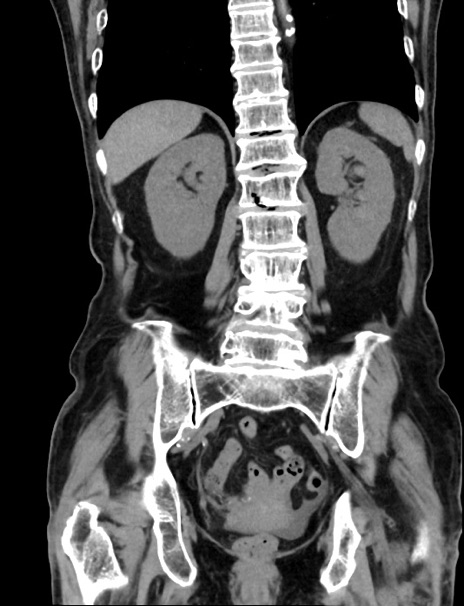

症例33(冠状断像)

【症例】70歳代 女性

【主訴】心窩部痛

【現病歴】延髄病変の精査・加療にて神経内科入院中。本日より心窩部痛あり。

【既往歴】虫垂炎

【身体所見】右下腹部を中心に圧痛と反跳痛あり。

【データ】WBC 10900、CRP 0.02